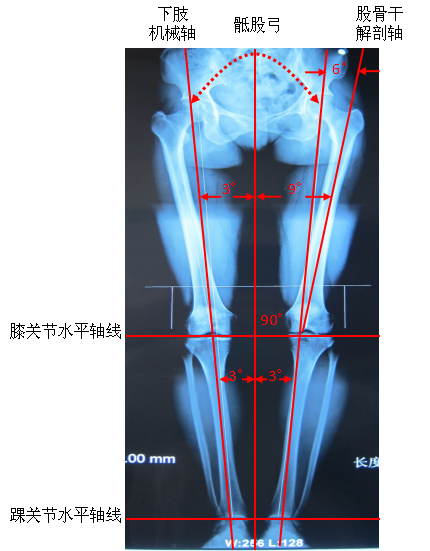

因为人体直立时,体重自腰椎、骶骨经两侧的骶髂关节、髋臼传导至两侧的股骨头,再由股骨头往下到达下肢。

正常情况下重力线通过膝关节胫股关节面中心,关节活动时通过膝关节的负荷量为体重的2~3倍。腰椎、骨盆劳损病变会导致膝关节正常承重力线的改变,使得关节面应力不均匀,造成关节、软骨退变,加速骨性关节炎的发生。所以治疗本病还应重视调整患者脊柱、骨盆力学平衡。

治疗前后膝内翻角度比较

治疗前 治疗后